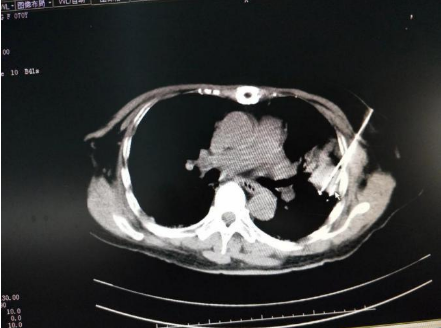

随后李阿姨入住暨南大学附属复大肿瘤医院,牛立志博士会诊后立即制定氩氦刀冷冻治疗方案。9月12日牛博士主刀,带领复大冷冻治疗团队对李阿姨进行了冷冻手术治疗。当日9点时,团队以丰富的经验和精湛的冷冻技术对患者实施了正确有效的治疗,手术过程非常顺利,术中仅出血0.5ml,生命体征平稳。

手术进行时:左肺癌氩氦刀冷冻治疗术